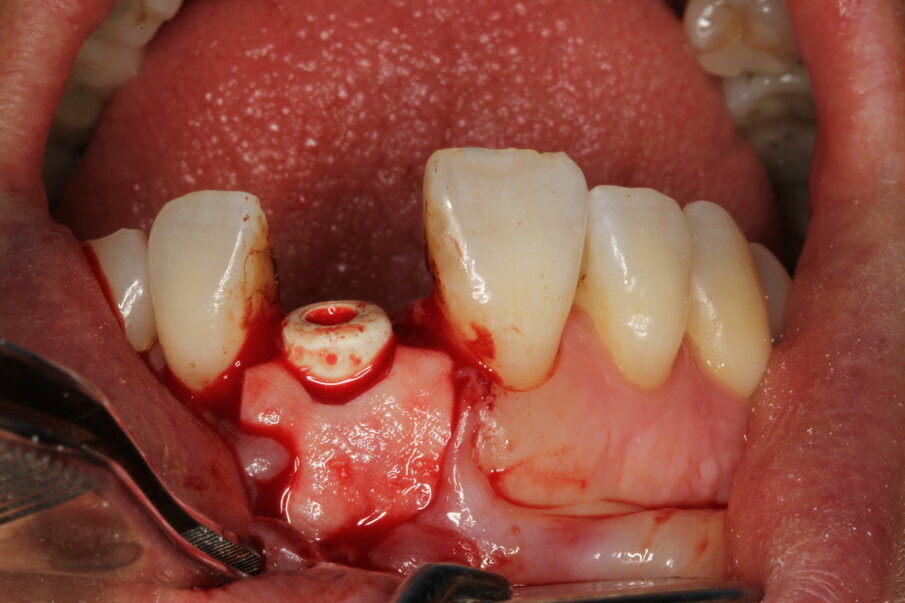

Local anaesthesia was performed with 2% mepivacaine with 1:100,000 adrenaline. Preventative antibiotic therapy with amoxicillin (1 g, b.d. for five days) was prescribed, aided by use of a 0.2 % chlorhexidine mouthrinse three times a day for one minute. The tooth was extracted and the sulcular epithelium removed with diamond burs. The milled surgical template (Figs. 12 & 13) served as a guide for the first 2 mm diameter pilot drill (Fig. 14). Thus, the planned depth, position and angulation of the osteotomy were obtained. The drill sequence was completed freehand, using tapered 3.0 and 3.4 mm drills. A Neoss Pro- Active Tapered Implant of 4 mm in diameter and 13 mm in length was inserted flush with the mesial/palatal/distal bone, motor driven up to a torque of 50 Ncm and then with a manual wrench (Fig. 15). The correct position of the internal hex was verified by checking the references on the implant driver, which ideally points in the buccal direction. Resonance frequency analysis with Penguin RFA (Integration Diagnostics Sweden) determined an ISQ value of 73/76. At this stage, a Neoss Esthetic Healing Abutment with a ScanPeg was connected to the implant (Fig. 16). A flap was then raised after a vertical incision of the frenulum and the expected buccal exposure of the implant neck was evident. Autogenous bone harvested from the drills was positioned directly on the implant surface (Fig. 17), followed by a bone substitute on top of it and on the buccal cortical bone (Fig. 18). This material was covered with a resorbable membrane (Fig. 19). The mobilised flap was then repositioned by rotating it coronally and fixed with single sutures (Fig. 20). The removable partial denture was adapted and delivered (Fig. 21). An immediate postoperative CBCT scan of 60 x 60 mm was performed, and it confirmed a perfectly centred implant position (Figs. 22 & 23).